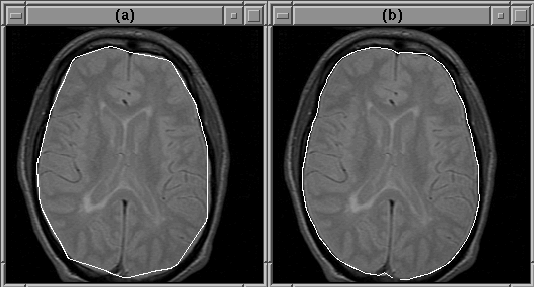

Figure 5.6 shows the results of the active contour algorithm on slice 16 of Data Set 1 (see Section 8.2). The algorithm converged in about 5 iterations and has reasonably located the intracranial boundary. The initial guess in this case was very good.

Figure 5.6: An active contour can detect the intracranial boundary. (a) The initial guess. (b) The converged contour.

Figure 5.7 shows the results of the algorithm when the initial guess is not that good. In this case, the intracranial boundary has obviously been missed.

Figure 5.7: An active contour will miss the intracranial boundary if the initial guess is bad. (a) The initial guess. (b) The converged contour.